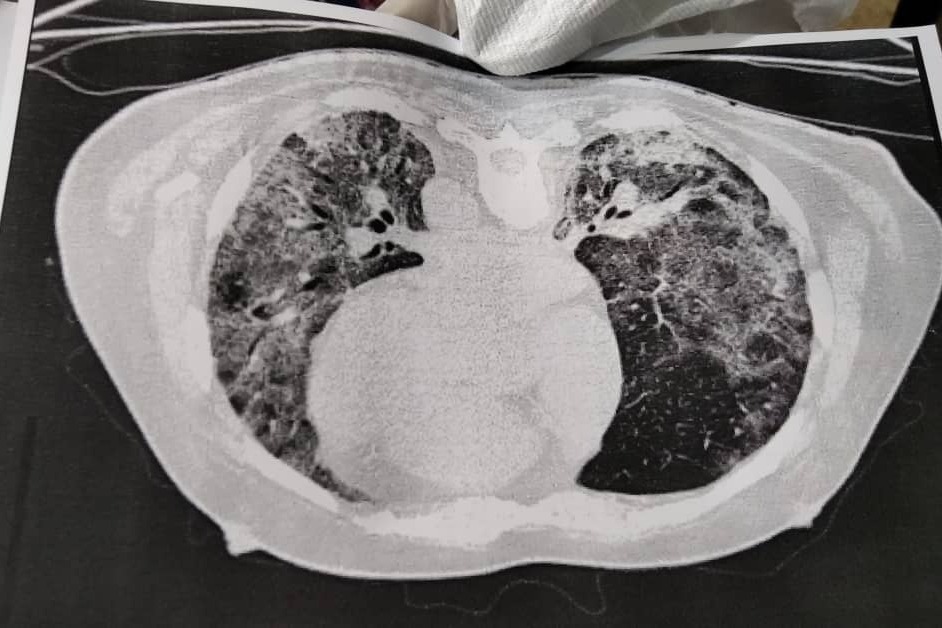

El 31 de agosto mi padre fue diagnosticado con neumonía bilateral vinculada al Covid-19. Si bien le aplicamos el tratamiento en casa, el lunes 14 tuvo que ser hospitalizado porque la infección respiratoria no cedía. Ahora, el médico tratante recomienda 5 días de terapia intensiva ante fallo respiratorio y hemodinámico, por bradicardia extrema, con falla multiorgánica por sepsis.

On August 31, my father was diagnosed with bilateral pneumonia linked to Covid-19. Although we applied the treatment at home, on Monday the 14th he had to be hospitalized because the respiratory infection did not subside. Now, the treating physician recommends 5 days of intensive therapy for respiratory and hemodynamic failure, for extreme bradycardia, with multiorgan failure due to sepsis.

El 31 de agosto mi padre fue diagnosticado con neumonía bilateral vinculada al Covid-19. Si bien le aplicamos el tratamiento en casa, el lunes 14 tuvo que ser hospitalizado porque la infección respiratoria no cedía. Ahora, el médico tratante recomienda 5 días de terapia intensiva ante fallo respiratorio y hemodinámico, por bradicardia extrema, con falla multiorgánica por sepsis.

On August 31, my father was diagnosed with bilateral pneumonia linked to Covid-19. Although we applied the treatment at home, on Monday the 14th he had to be hospitalized because the respiratory infection did not subside. Now, the treating physician recommends 5 days of intensive therapy for respiratory and hemodynamic failure, for extreme bradycardia, with multiorgan failure due to sepsis.